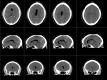

Figure 4

Series of CT brain slices—incidental finding representing a lipoma of the corpus callosum.